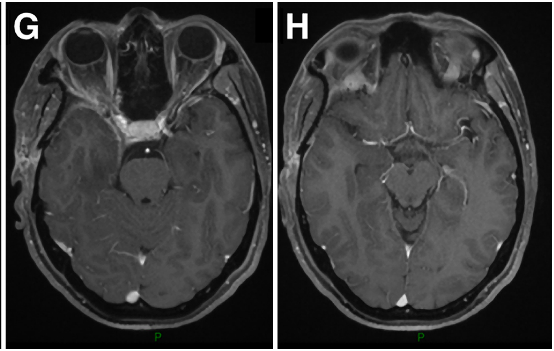

41岁男性,蝶眶脑膜瘤继发眼球突出,并延伸至前床突和蝶窦(SphS)。

图1A-D:术前MR显示蝶眶区脑膜瘤占位,增强病灶,浸润延伸至蝶腭窝(黄色箭头)。

术中操作:Froelich教授经翼点入路开颅,剥离海绵窦侧壁后,行硬膜外前床突切除术。切除硬脑膜内肿瘤及侵袭硬脑膜及眶周的肿瘤。使用颅包膜补片对硬脑膜缺损进行水密封闭后,剥去圆孔(FR),暴露翼腭窝(PPF)。肿瘤沿V2神经鞘播散生长,磨除上颌窦(MaxS)后,打开蝶窦(SphS)。

术后组织病理学:I级脑膜上皮型脑膜瘤。

术后临床情况:眼球突出症状立即好转,术后恢复好,病程平稳。术后V2神经功能包括角膜感觉正常,无干眼、流泪异常等症状,按期拆线出院。

▼术后影像复查:证实肿瘤被完全切除。E-H:术后轴位MR图像显示肿瘤完全切除。